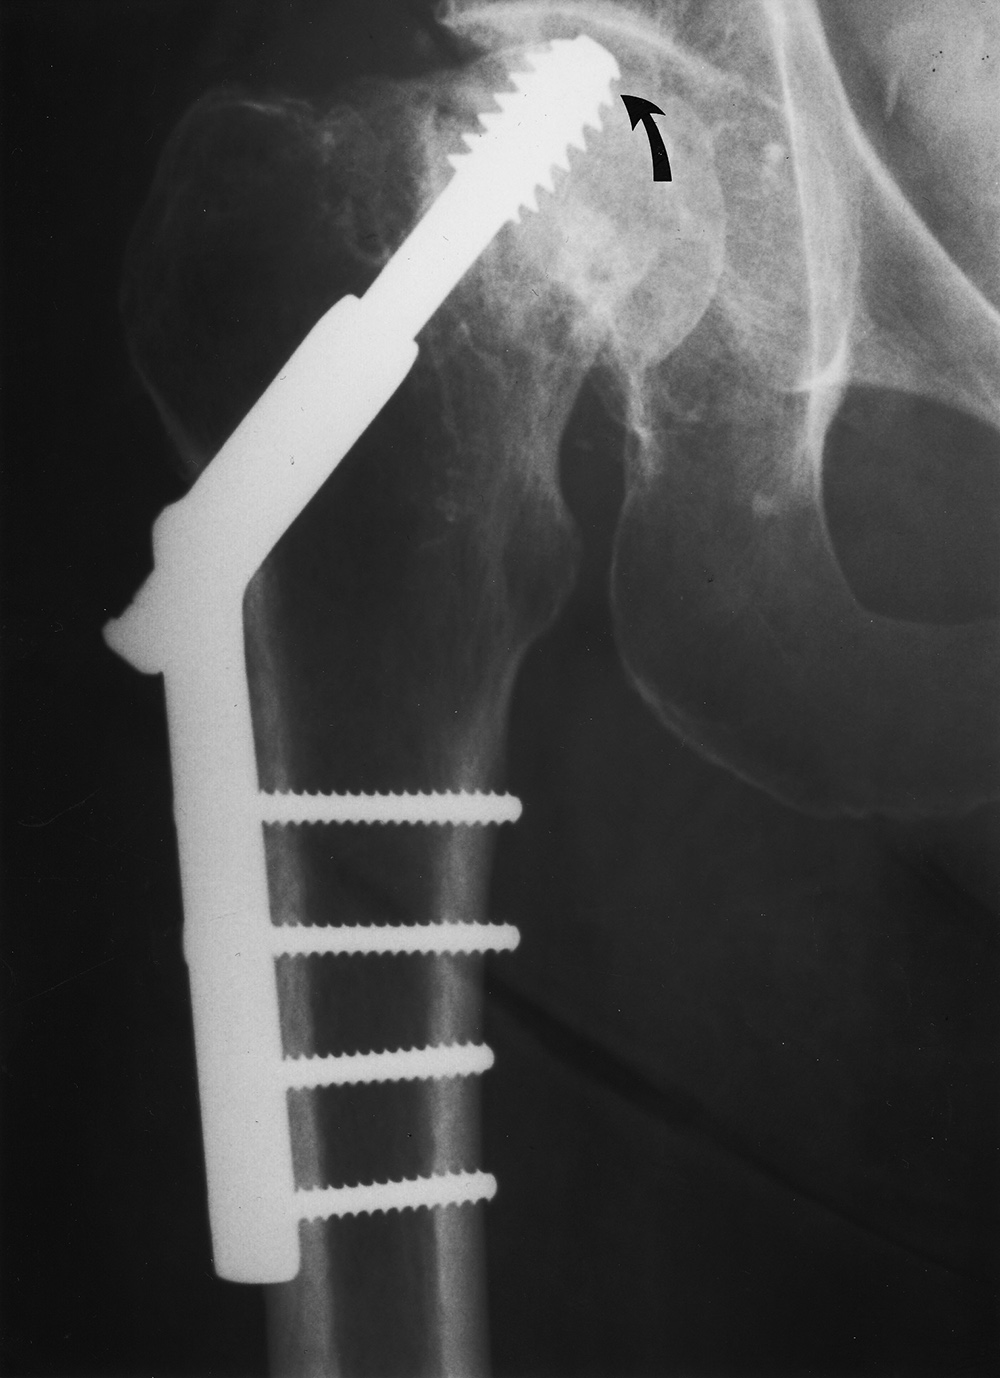

| The compression screw has slid distally in the barrel as it was designed to do when the femoral neck fracture site becomes compressed. This did not prevent the screw from cutting out of the femoral head (curved arrow). From Hunter, 1994 |